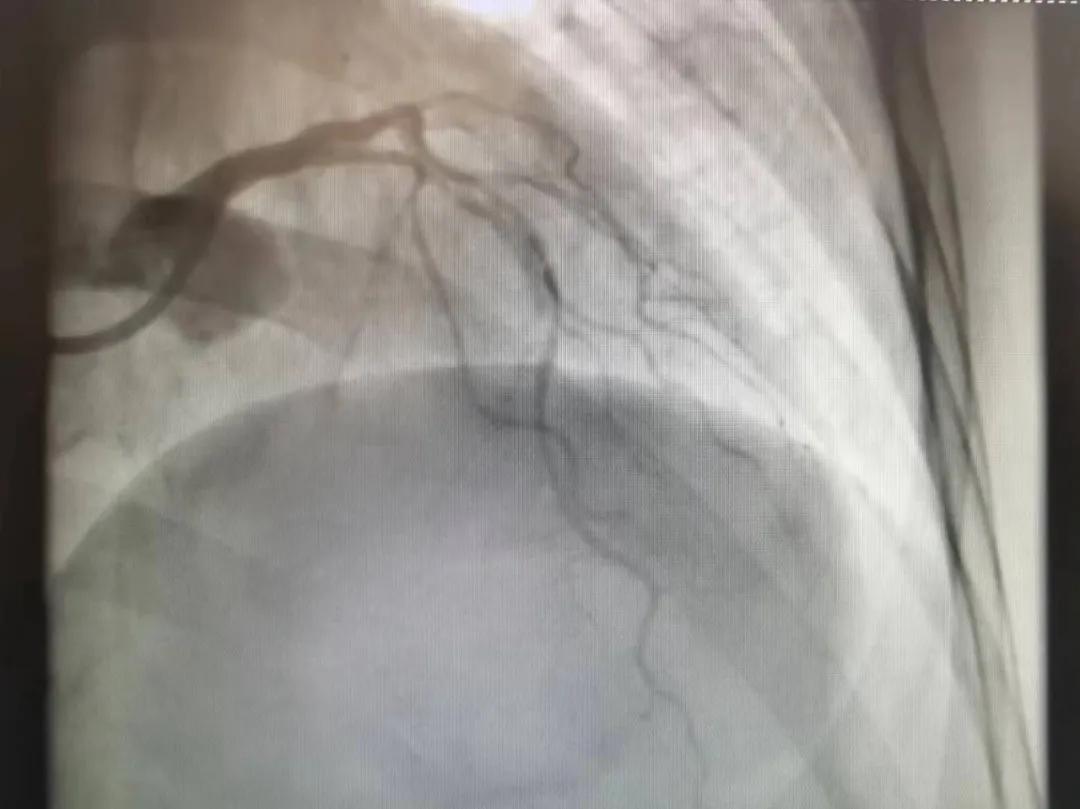

病人是位六十多歲的女性患者,有長期高血壓病史,1個月前開始出現(xiàn)胸悶胸痛,口服藥物治療效果不佳,經(jīng)朋友介紹,來到市二院心血管內(nèi)科。入院后完善冠狀動脈造影提示:前降支全程彌漫性狹窄伴鈣化,最重95%,回旋支狹窄約85%,右冠脈全程狹窄伴鈣化,最重60%。血管內(nèi)超聲顯示右冠脈開口面積3.36mm²,可見環(huán)形鈣化,考慮患者病變程度重、鈣化明顯,常規(guī)器械無法實現(xiàn)病變的良好預處理,且有很高的冠脈穿孔、血管夾層的風險。

術前